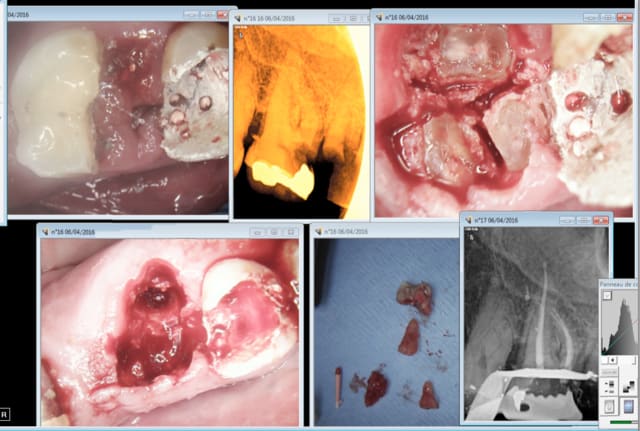

Une histoire vrais

Patiente d'une trentaine d'année qui consulte pour un problème de protrusion dentaire.

Elle à était traité par un dentiste qui a régler l'encombrement dentaire antérieur sup ET la protrusion en passant les dents au taille crayon et en réalisant des couronne angulé palatinement.

Le seul soucie c'est que les incisives paraisse ultra mince et que c'est moche.

J'ai due expliquer à la patient qu'a moins de refaire les trois couronne pour restaurer une anatomie et angulation naturelle je ne pouvrais pas faire grand chose.

Le plan de traitement :

Enlay, Chico, worg fermer les yeux c'est la partie qui fait peur .

- Extraction de 14 et 24

Mes mignonettes vous pouvez sortir les têtes des coussins et respirer le danger est passé.

- Extraction de 36 et 46

- Extraction de 38 (compliqué rapport avec le nerf)

- dépose des couronnes, reprise des traitement endo et réalisation de provisoire avec une angulation correct.

- Distalisation des Canines pour se retrouver en class I et retraction des incisives en maintenant suffisament d'espace pour pouvoir augmenter le diamètre mesio distale de 11 et 21 de 2 mm.

- Pose d'implant pour remplacer 36 ( 47 et 48 seront mésialé à l'aide de minivise pour fermer les espaces ).

Un cas compliqué moyen (trois patientes le mois dernier avec des couronnes anterieur angulé en palatine par le dentiste précédent ).